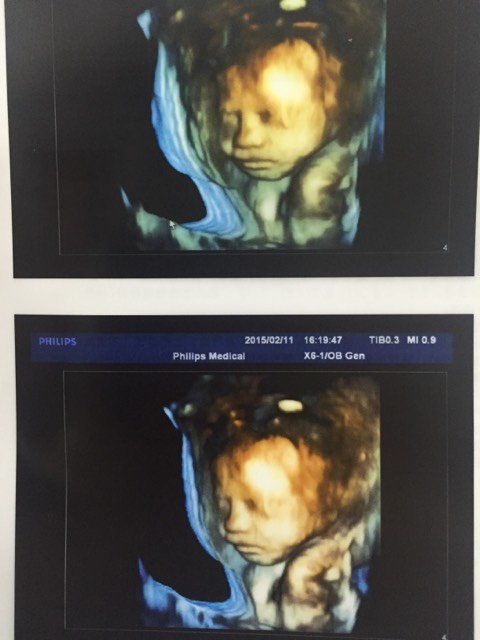

我的小宝宝,做四维医生说心脏有积液,比正常的多点,但又达不到医学诊断标准,叫我28周的时候再看!好

我的小宝宝,做四维医生说心脏有积液,比正常的多点,但又达不到医学诊断标准,叫我28周的时候再看!好担心哦!怎么半!我怕28周的时候完了!